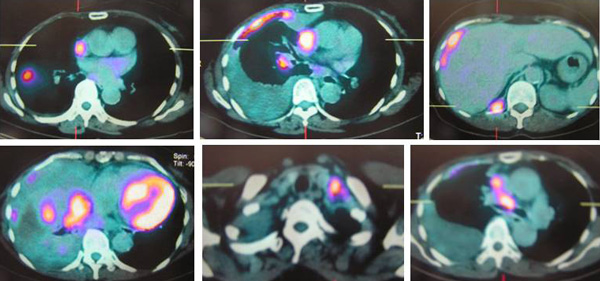

SH said she was well all these years and her progress was monitored by her doctor. About 10 years later, in early 2009, SH developed shortness of breath. She could not lift her left arm. She was tired and lost her appetite. A chest X-ray indicated large left pleural effusion. SH had the fluid in her lung tapped out. A CT scan on 7 January 2009 indicated several subcentimeter nodules in her left lung. The lymph nodes in the left axilla and aortopulmonary window were enlarged. Impression: left pulmonary and pleural metastasis.

SH sought a second opinion from another oncologist at a university hospital. Another CT scan was performed and it also confirmed a metastatic breast cancer with left pleural effusion with small benign liver cysts.

A bone scan done on 29 January 2009 indicated multiple skeletal metastases in the sternum and two ribs on the left side.

In August 2011 SH developed shortness of breath again. A CT scan on 4 August 2011 confirmed presence of mild left pleural effusion. Fluid was tapped out of her lung again.

A bone scan done on 18 March 2011 indicated “sclerotic bone metastases in manubrium showing activity.” SH was told that if Aromasin did not work for her, she would have to undergo intravenous chemotherapy.